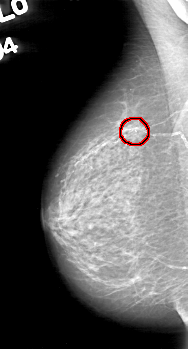

FILE: D_4044_1.RIGHT_MLO.OVERLAY

TOTAL_ABNORMALITIES 1

ABNORMALITY 1

LESION_TYPE CALCIFICATION TYPE COARSE DISTRIBUTION CLUSTERED

ASSESSMENT 0

SUBTLETY 5

PATHOLOGY BENIGN

TOTAL_OUTLINES 1

BOUNDARY